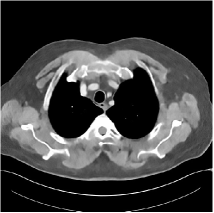

Refer to caption WavResNet [11]Refer to caption WavResNet [11]Refer to caption WavResNet [11]Refer to caption Momentum-Net (SimpleCNN)Refer to caption Momentum-Net (SimpleCNN)Refer to caption Momentum-Net (SimpleCNN)Refer to caption Momentum-Net (SimpleCNN-RSN)Refer to caption Momentum-Net (SimpleCNN-RSN)Refer to caption Momentum-Net (SimpleCNN-RSN)Refer to caption Momentum-Net (Dn-RSN)Refer to caption Momentum-Net (Dn-RSN)Refer to caption Momentum-Net (Dn-RSN)Refer to caption ReferenceRefer to caption ReferenceRefer to caption Reference

Refer to caption Refer to caption Refer to caption Refer to caption Refer to caption Refer to caption Refer to caption Refer to caption Refer to caption Refer to caption Refer to caption Refer to caption Refer to caption Refer to caption Refer to caption

Fig. 3: Three examples (from top to bottom) of the reconstructed testing images using Momentum-Net with SimpleCNN (the second column), with SimpleCNN-RSN (the third column), and with Dn-RSN (the fourth column). The compared WavResNet denoised images are shown in the first column, and the reference images are in the fifth column. See their FBP images in Fig. 4.

3.2 Proposed Momentum-Net with SimpleCNN

Fig. 2 shows that the proposed Momentum-Net with SimpleCNN decreases RMSE dramatically in the first 30 layers, and tends to converge in 50 layers. The Momentum-Net reduces the mean RMSE value by 4.5 HU and gives smaller standard deviations in RMSE, compared to WavResNet, as reported in Table 1. This implies that the proposed Momentum-Net with SimpleCNN can improve both the accuracy and stability of low-dose CT image reconstruction than a state-of-the-art image denoising deep NN, WavResNet. The proposed Momentum-Net with SimpleCNN better removes noise and streak artifacts than WavResNet. It also provides clearer reconstructions of some details; see, in Fig. 3, the boundaries shown in the zoomed region at the top-right corner in the first example, the arrow pointed structures in zoomed areas of the second example, and the arrow pointed tissues in the left zoomed region in the third example.

3.3 Momentum-Nets involving RSN-based training

We show the reconstructed examples by Momentum-Net with SimpleCNN-RSN and Dn-RSN in the third and fourth columns of Fig. 3 respectively. Comparing the first three and the last columns in Fig. 3, we observe that Momentum-Net with SimpleCNN-RSN provides generally noisier reconstructions than WavResNet and Momentum-Net with SimpleCNN. However, Momentum-Net with SimpleCNN-RSN sometimes can provide clearer details than WavResNet. For example, in the right zoomed box of the second example, Momentum-Net with SimpleCNN-RSN shows better reconstruction quality for the arrow pointed structures than WavResNet, and in the left zoomed box in the third row, the former gives clearer small tissues marked by red arrows than the latter. Table 1 reports that Momentum-Net with SimpleCNN-RSN is approximately 2.9 RMSE (HU) higher than WavResNet, while it has smaller standard deviations. This implies that Momentum-Net with SimpleCNN-RSN is more stable than WavResNet, although it may not provide better image qualities. Momentum-Net with Dn-RSN, however, provides the worst visual and numerical results among the compared four methods in this paper.